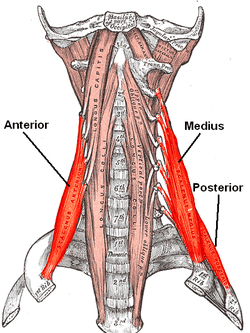

The anterior vertebral muscles. | |

The scalene muscles (from Greek σκαληνός, or skalenos, meaning uneven[1] as the pairs are all of differing length[2]) are a group of three pairs of muscles in the lateral neck, namely the anterior scalene, middle scalene, and posterior scalene. They are innervated by the fourth, fifth, and sixth cervical spinal nerves (C4-C6).

The scalene muscles originate from the transverse processes from the cervical vertebrae of C2 to C7 and insert onto the first and second ribs, and used to be known as the lateral vertebral muscles.[3]

Anterior scalene

Middle scalene

Posterior scalene